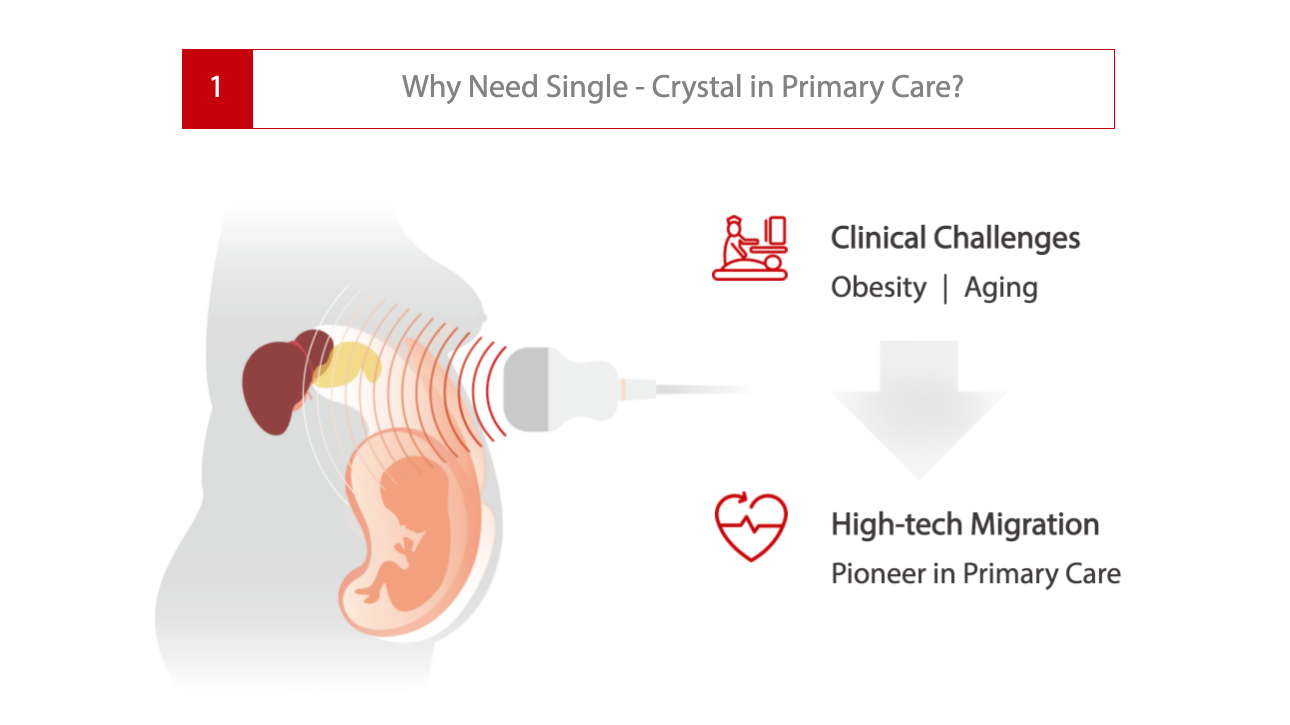

Soins primaires avec Pure Crystal

Niveau Monocristal